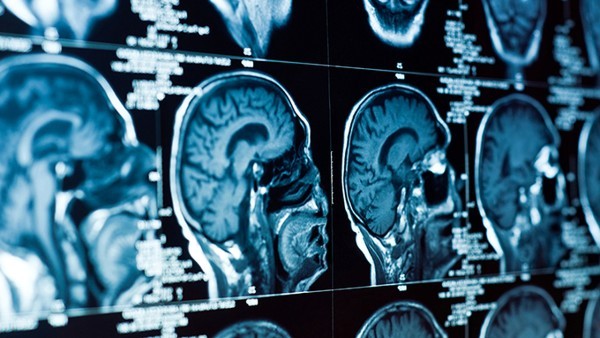

隐性梅毒又称潜伏梅毒,是指无临床症状或临床症状已消失,除梅毒血清学阳性外无任何阳性体征,且脑脊液检查正常者称为隐性梅毒。隐性梅毒对人体的危害主要是神经系统损害,包括脑神经梅毒、脊神经梅毒、脑膜血管梅毒,根据损害部位不同,患者可出现不同的临床表现。

1、脑神经梅毒:脑神经梅毒是最常见的神经系统梅毒,通常是由于感染苍白密螺旋体引起的,一般是通过胎盘传染而来,患者在感染梅毒1-2年后开始出现症状,通常表现为脑膜炎、脑膜血管梅毒、脑神经梅毒和脊髓痨。患者可出现不自主的颅神经损害表现,如头痛、恶心、呕吐、视力下降、听力下降、认知下降,严重者可出现精神行为异常、躁狂、谵妄等;

2、脊神经梅毒:脊神经梅毒通常是由于感染后未经治疗,或治疗不彻底导致的,一般表现为肋间神经性疼痛,腰穿检查可发现脊髓痨。部分患者脊髓受到损害后,可出现下肢瘫痪、排尿障碍、感觉障碍等;

3、脑膜血管梅毒:脑膜血管梅毒可分为脑膜血管梅毒和脑膜血管膜血管梅毒,脑膜血管梅毒症状较为严重,可出现头痛、呕吐、颈项强直等颅内压增高的症状,还可伴有脑膜刺激征。当脑膜血管被侵犯时,还可出现相应的脑膜刺激征;